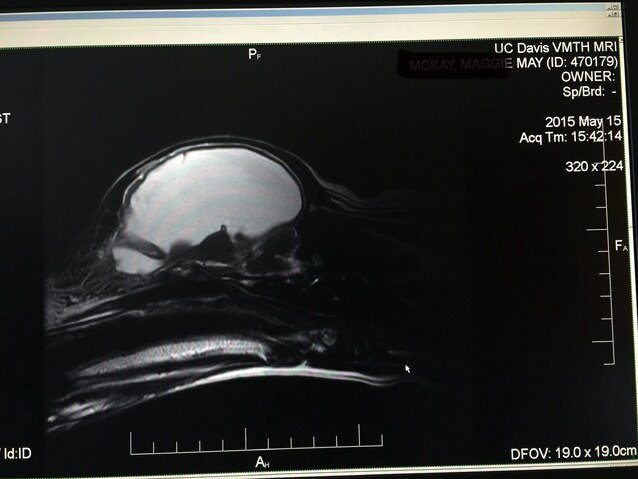

La risonanza che ha sorpreso i veterinari

Dopo la crisi, Maggie è stata portata dal veterinario. Gli esami del sangue hanno rivelato un dato anomalo: livelli di sodio estremamente bassi. È stata quindi inviata alla UC Davis School of Veterinary Medicine, uno dei centri veterinari universitari più importanti degli Stati Uniti, per ulteriori approfondimenti.

Qui i medici hanno eseguito una risonanza magnetica (MRI) e il risultato è stato sorprendente: circa il 95% della sua cavità cranica era occupato da liquido, non da tessuto cerebrale.

Nelle immagini, quasi tutto ciò che normalmente dovrebbe essere cervello appariva bianco: era liquido cerebrospinale, il fluido che normalmente circonda e protegge cervello e midollo spinale. La diagnosi definitiva: idrocefalo.